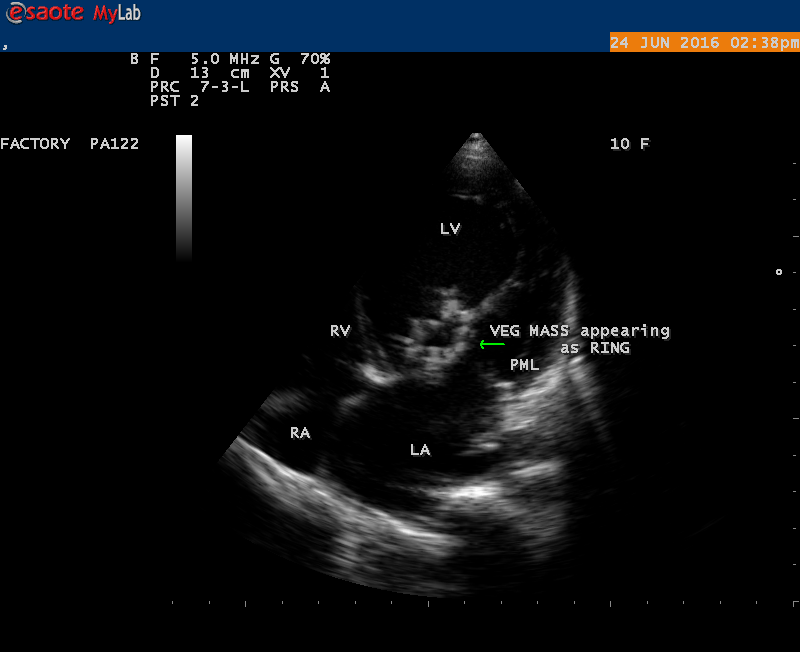

A 10 year female child was referred for echocardiographic evaluation with an apical systolic murmur. The child was having recurrent episodes of rheumatic fever (febrile illness with joint pains) at the age of 5-6 years and taken some treatment from the local medical practitioner, but she was not taken penicillin prophylaxis earlier. The child was remained afebrile for long period and no precipitating factors of infective endocarditis such as dental or genitourinary procedures in the past. General examination revealed normal growth and development, no cyanosis and clubbing and peripheral signs of infective endocarditis such s Osler’s nodes, Janeway lesions, Roths spots and splinter haemorrhages are not present and they are relatively rare in children. Physical examination revealed a grade 3/6 , blowing, high pitched, holosystolic murmur with a constant intensity and duration on dynamic auscultation and loudest at the apex with a radiation to left axilla and transmitted to the left infrascapular area and vertebral coloumn and it is due to the flow generating the murmur is directed posterolaterally within the left atrial cavity, suggesting the murmur of mitral regurgitation due to the rupture of chordae tendineae of anterior mitral leaflet. Blood culture revealed normal. Blood chemistry revealed the positive serum ASO titer, suggesting a recent streptococcal infection and other parameters are normal. X- ray chest reveled moderate cardiomegaly and ECG revealed a left ventricular volume overload pattern of eccentric hypertrophy due to LV dilatation as a result of severe mitral regurgitation and a normal rhythm. Transthoracic echocardiography revealed a giant vegetation ‘popcorn’ like in Figures 1,3 and 4 and ‘cucumber’ like in Figure 2, mainly attached to base and apical portion of anterior mitral leaflet as shown in Figure 31 and manifested in various size and shapes as shown in Figures 1 to 33. A flail anterior leaflet with a disorganized mitral regurgitation jet as shown in Figure 16 and 21 and the posterior leaflet is embedded with vegetation and resulting in ‘kissing forms’ as shown in Figures 13, 14 and 15 in echocardiography imaging. Tricuspid valve is also thickened and calcified as shown in Figure 2 in addition to thickened and calcified mitral leaflets, suggesting an underlying rheumatic etiology predisposing to the formation of vegetation. The child was given 1.2 million units of intramuscular benzathine penicillin injection as a therapeutic and initial prophylaxis dose for rheumatic fever and advised every 3 weeks for life long. Small doses of digoxin and diuretics are also prescribed and advised early surgery (mitral valve replacement) Transthoracic 2D images are as in Figures 1 to 33 are given below

The most common and direct evidence of infective endocarditis is the vegetation and it begins as a microscopic focus of infection and gradually grows into a conspicuous mass. It is typically an irregularly shaped, highly mobile, echogenic mass attached to the free edge of a valve leaflet ( most commonly at the coaptation line) and tends to develop on the ‘upstream’ side of the valve leaflets ( ie, the ventricular side of aortic valve and the atrial side of mitral and tricuspid valves. They may be seesile or pedunculated, but usually has an oscillating or fluttering motion, a typical feature of most vegetations. Vegetation move with the leaflet in a more chaotic (‘oscillating’) manner and it may prolapse through the valve into the LV (left ventricle) as it opens as shown in Figures 3, 4 and 16 and into LA (left atrium) as it closing (Figure 5 and 6) . The mass of vegetation is typically homogeneous with echogenicity similar to that of the myocardium. The infectious process often alter the valvular structure and function. Extensive involvement of the leaflet may result in chordal rupture, leading to severe regurgitation as shown in Figure 21 . Direct and typical signs of RMCT (ruptured mitral chordate tendineae) were chain-flail or whiplash-like changes and had an incidence of 86.7%, causing severe regurgitation and mitral chordal rupture is the leading cause of flail mitral leaflet[30]. A large vegetation may obstruct the valve orifice as shown in Figure 1 and 2 , sometimes termed as “obstructive-type bacterial endocarditis” and producing a functional valve stenosis ( Ping-Pong mitral stenosis [31]) similar to left atrial myxoma as shown in Figure 29.

The size and shape of vegetation vary due to curling of vegetation. The size of vegetation in this child is 35.6 x 9.3 mm as in Figure 17 , 20 x 23.7 mm as in Figure 1 , 32.9 x 13.9 mm as in Figure 2 .

The shape of vegetation varies in this child as ‘popcorn’ like (Figures 1,3 and 4 ), rod-shaped (Figure ), basket shaped (Figure 7 )[33-Figure 13.3], ‘baby in hand’ appearance (Figure 18), ‘cucumber shaped (Figure 2 ) and a ‘bunch of plantain’appearance (Figure 33 ), ring shaped (Figure 19 }, bileaflet structure (Figure 9 )with bileaflet MR jet as shown in Figure 10 . and kissing forms (Figure 13 - parasternal long axis view, Figure 14 - apical four chamber view and Figure 15 - short axis view)